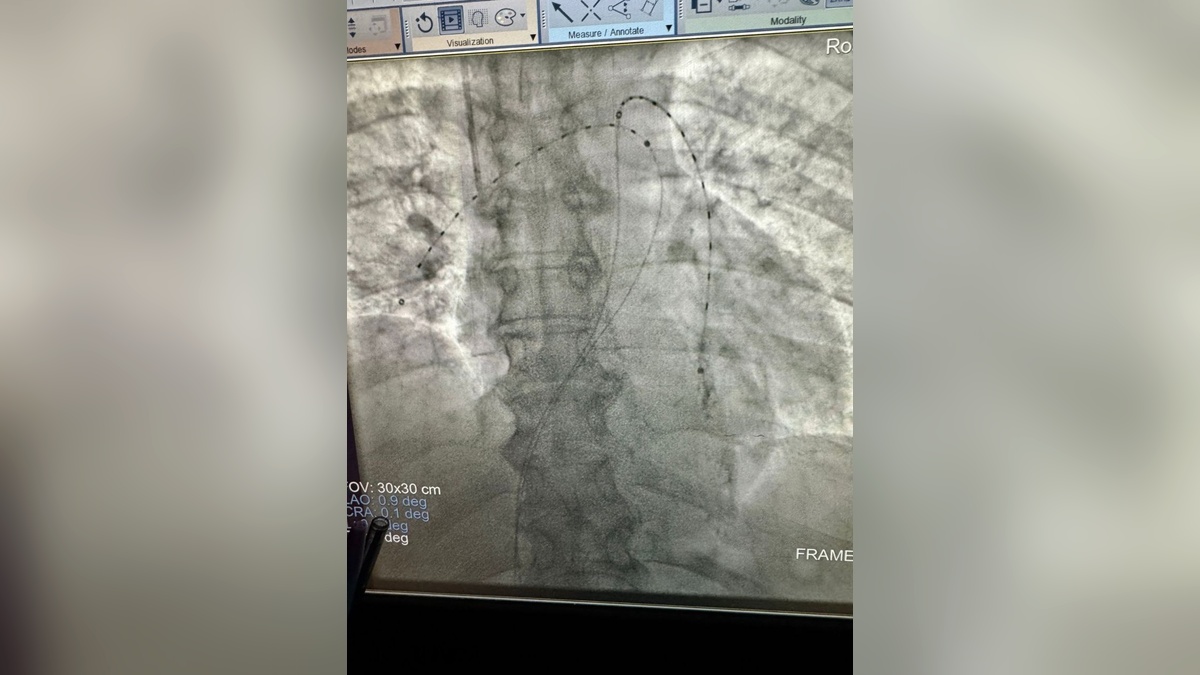

Врачи Краснодарской краевой больницы № 1 впервые в регионе провели процедуру ультразвукового катетерного тромболизиса (EKOS), спасшую 68-летнюю пациентку с тромбами в легких.

Женщина поступила в больницу с выраженной дыхательной недостаточностью. После обследования медики решили применить современную технологию EKOS для лечения тромбоэмболии легочной артерии — одного из наиболее опасных состояний в кардиологии с высокой смертностью и риском тяжелой инвалидности.

Процедура проводилась малоинвазивным способом под местным обезболиванием. Через два прокола бедренных вен специалисты ввели инфузионные катетеры в правую и левую легочные артерии, поместив в них ультразвуковые сердечники. Эта методика основана на комбинированном воздействии: ультразвук разрыхляет тромб, а небольшие дозы тромболитика аккуратно его растворяют. Операция длилась семь часов.

На следующее утро у пациентки наблюдалась положительная динамика: снизилось давление в легочной артерии, уменьшились размеры правого желудочка и нижней полой вены, сообщает пресс-служба НИИ-ККБ №1 имени Очаповского в Telegram.